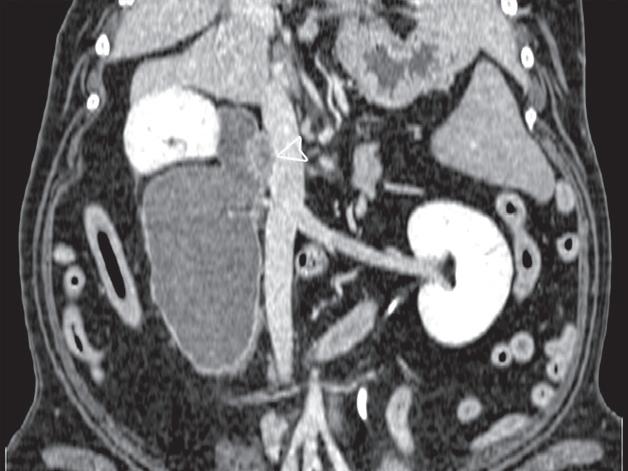

Badanie wykonano u 7-letniego rottweilera z rozpoznanym guzem nadnercza oraz nagłymi objawami dyskomfortu jamy brzusznej. Obrazy na ryc. a–c uporządkowano od strony doczaszkowej do doogonowej. Nadnercze prawe jest powiększone (a, d – otwarty grot strzałki) i ma widoczną ekscentryczną komponentę torbielowatą o densyjności płynu, która rozchodzi się doogonowo (a, b – strzałki). Tkanka miękka rozrostu oraz torebka nadnercza wykazują obwodowe wzmocnienie pokontrastowe. Torbielowata komponenta zmiany rozrostowej widoczna na obrazie odpowiada krwotokowi, który rozciąga się doogonowo w przestrzeni zaotrzewnowej (d). Dobrzusznie od zmiany widoczny jest moczowód (b – grot strzałki). Diagnoza makroskopowa i histologiczna została potwierdzona po chirurgicznym usunięciu zmiany (e – strzałka). Proszę zwrócić uwagę na porównanie obrazu TK zmiany (d) z wyciętym preparatem makroskopowym (f)